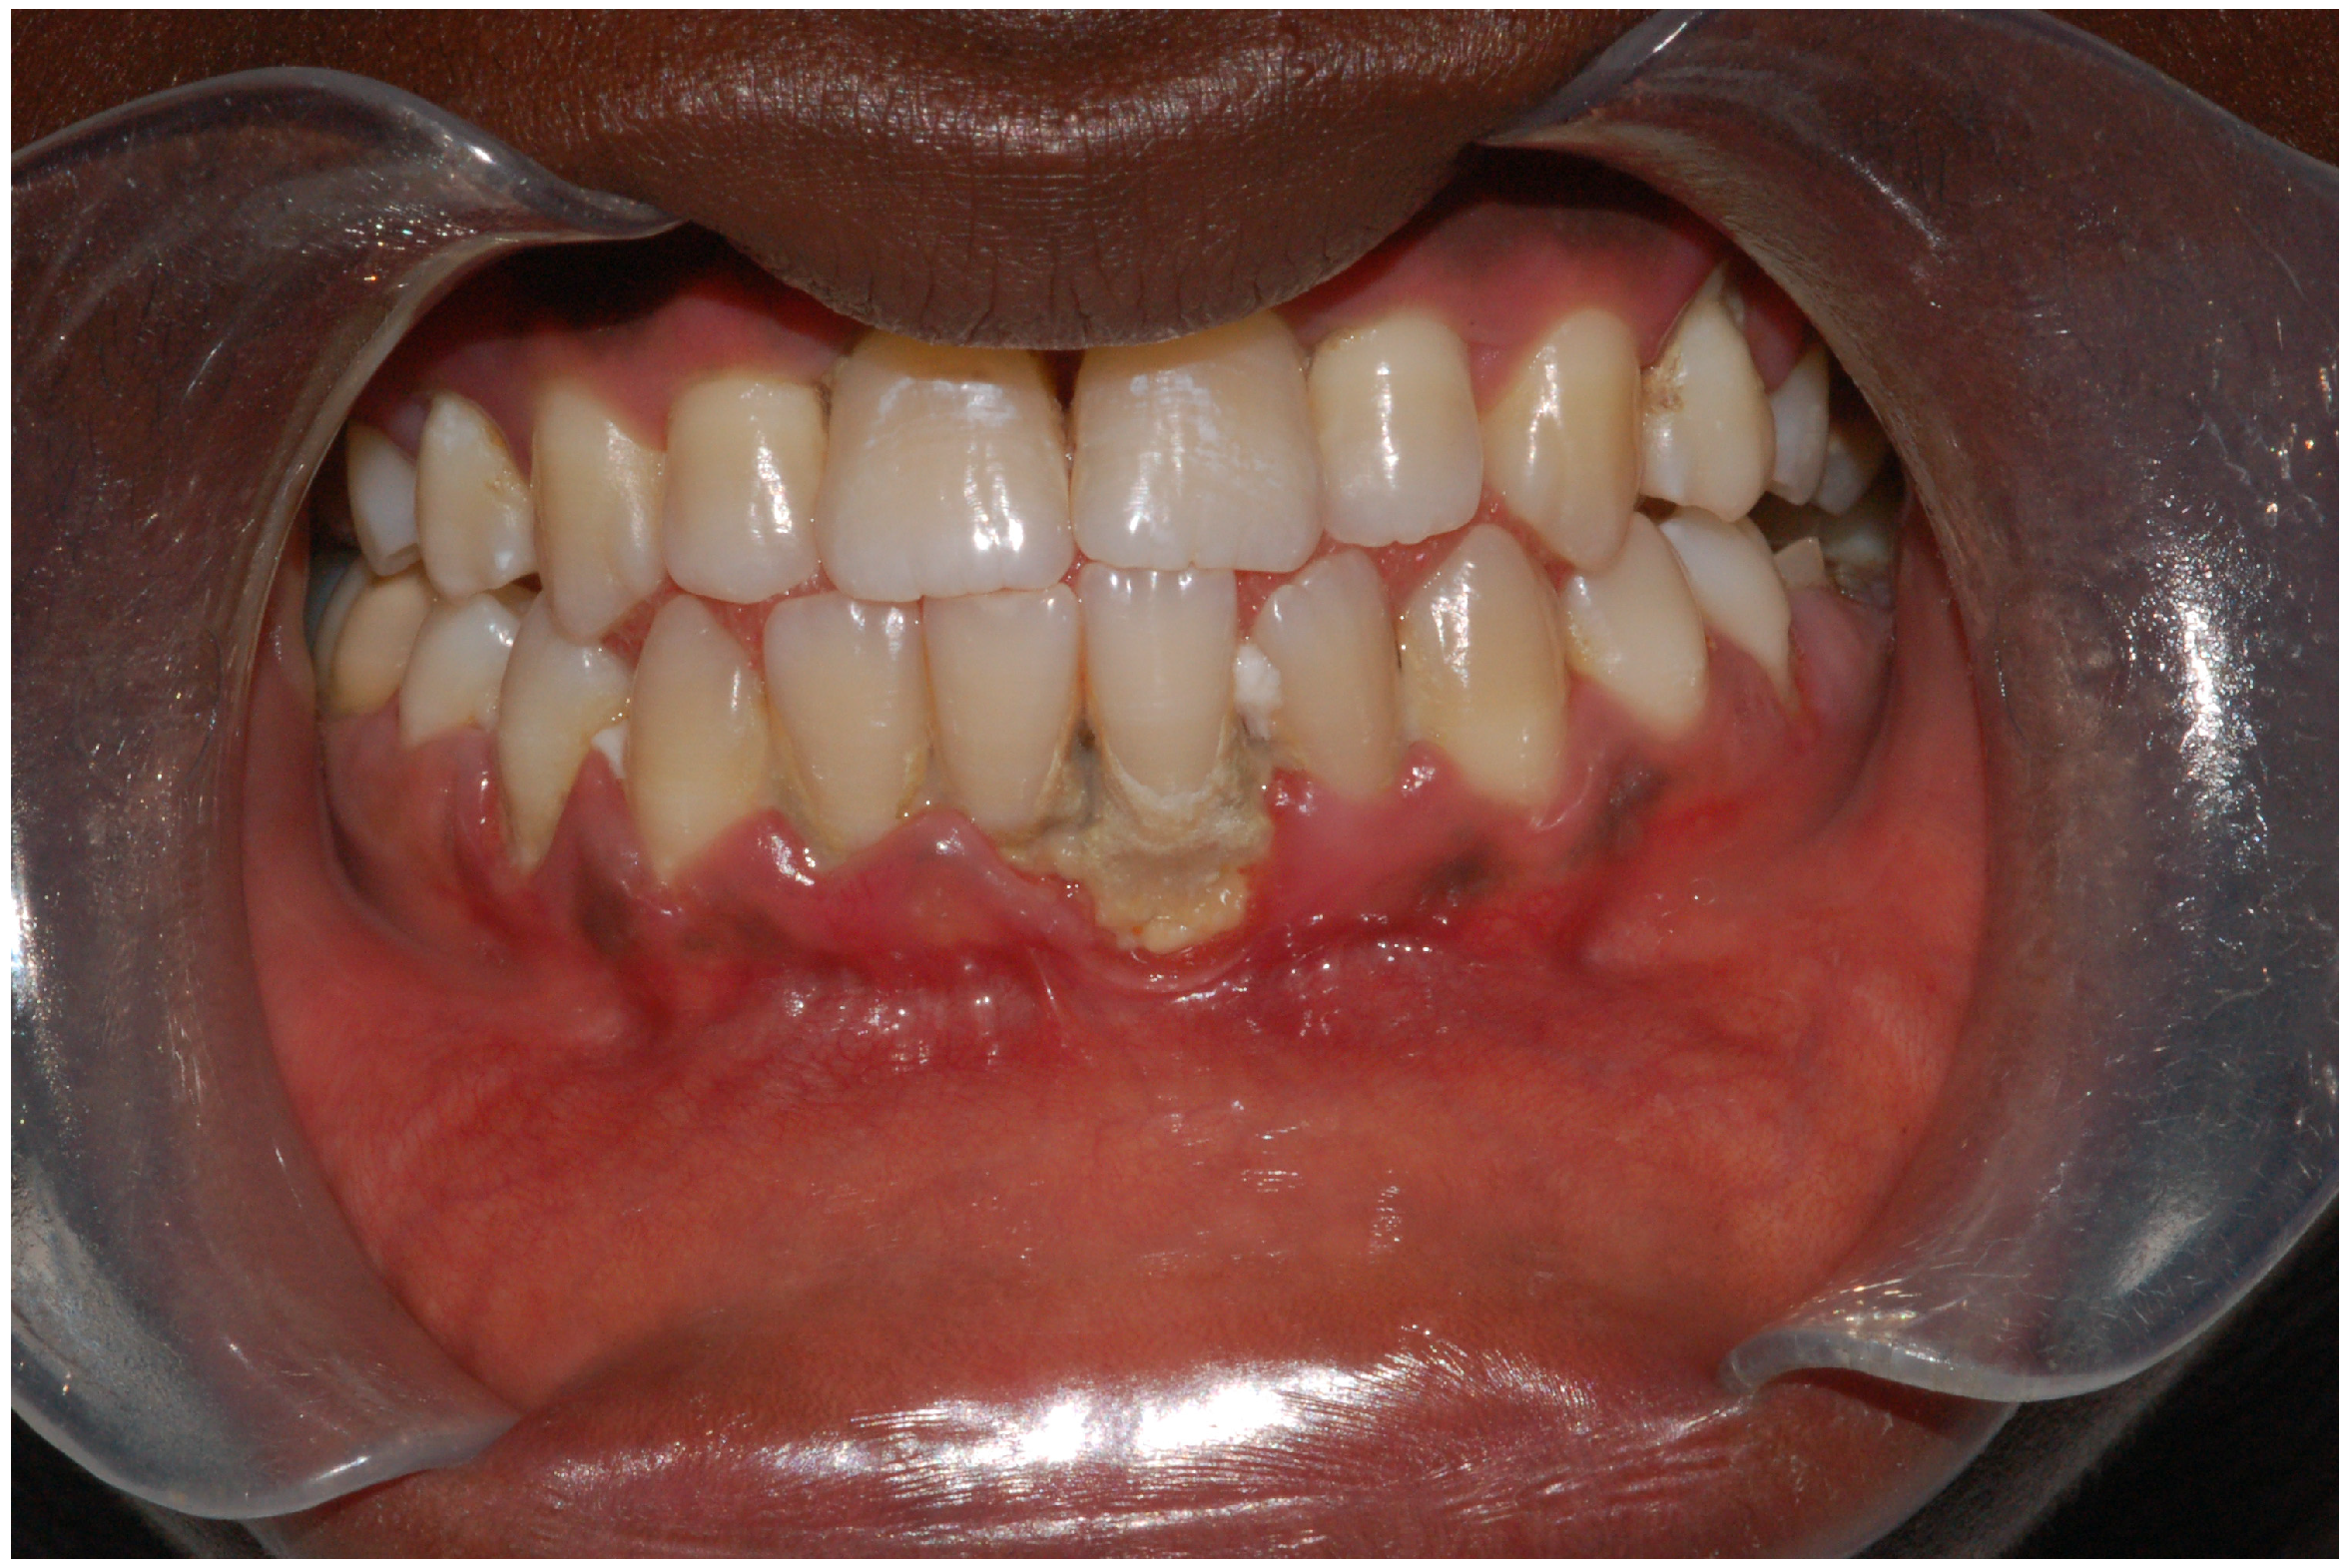

| IDA-CP patients displayed elevated gingival index values, bleeding on probing, probing pocket depth, and percentages (%) of sites with clinical attachment loss compared to CP patients. Moreover, the mean salivary and serum SOD levels were notably lower in IDA-PH, CP, and IDA-CP patients compared to the control group (CG). | [67] | |

| IDA patients had significantly higher frequencies of all oral manifestations than healthy controls; a burning sensation of oral mucosa, lingual varicosity, dry mouth, oral lichen planus, and atrophic glossitis were the five leading oral manifestations for IDA patients. | [60] | |

| ID predisposed patients to a high incidence of Candida infection and showed a variety of oral manifestations including angular cheilitis, atrophic glossitis, pseudomembranous candidosis, erythematous candidosis, median rhomboid glossitis, chronic mucocutaneous candidosis, papillary hyperplastic candidosis, and cheilocandidosis. | [72] | |